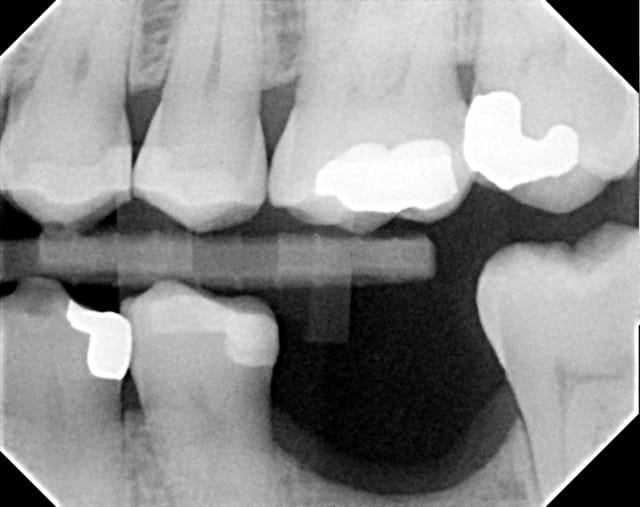

Contrôle post-op 2 ans.... reformation osseuse....

les 2 dernières radiographie sont inversées pour l'ordre chronologique

Avril 2010 i86phq - Eugenol